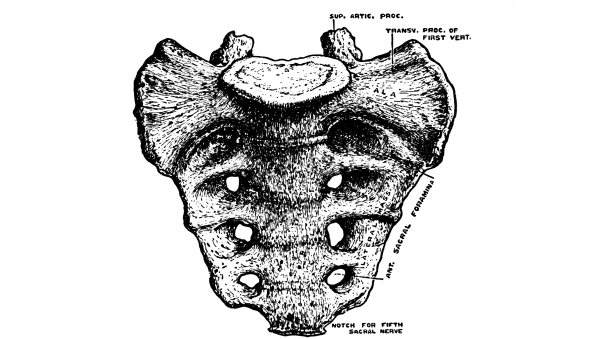

The Cerebrum, 75—The Cerebellum, 78—Pons Variolii, 78—Medulla Oblongata, 78—Spinal Cord, 79—Brain-centers, 81—Motor Tract, 82—Sensory Tract, 82—Reflex Action, 83—Cranial Nerves, 83—Spinal Nerves, 84—Brachial Plexus, 85—Sacral Plexus, 85—The Sympathetic System, 87—The Sympathetic Nerves, 87. |

The Pelvis, 161—The Male Generative Organs, 164—The Prostate Gland, 164—The Testes, 165—The Penis, 165—The Female Generative Organs, 165—The Ovaries, 165—The Fallopian Tubes, 166—The Uterus, 167—The Vagina, 168—The External Genitalia in the Female, 169—The Vulva, 169—The Mons Veneris, 169—The Labia Majora, 169—The Labia Minora, 170—The Clitoris, 170—The Meatus Urinarius, 170—The Hymen, 170—The Fourchette, 170—The Perineal Body, 170—The Perineum, 170. |